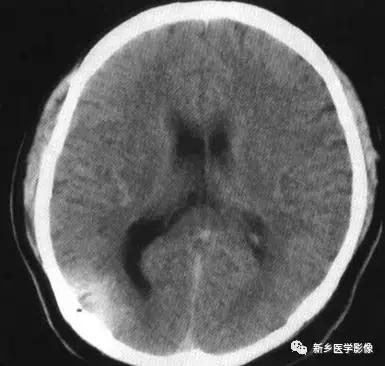

(1)前脑无裂畸形: (holoprosencephaly)是指一系列位于中线程度不同的畸形,累及大脑、面部、脑于和小脑.前脑未能够分开,呈不全性或完全性,端脑和间脑无法区分。根据脑及面部畸形程度将其分为无叶型、半叶型和单叶型。

无叶型前脑无裂畸形最严重.端脑半球间没有裂隙,呈马蹄形或新月形扩大的单脑室跨越中线,与背侧囊交通。丘脑互相融合,面部畸形从两眼距离过近到独眼畸形.往往死于胎儿或新生儿期。

半叶型前脑无裂畸形在前脑可见部分裂隙. 形成不同发育程度的大脑纵裂及大脑镰。两侧大脑半球在前部未完全分开,但枕叶和 双侧侧脑室体部分离,丘脑分开不完全。三脑室和海马发育不全,胼胝体仅可见到压部,而其他部分缺如.额叶和基底节前部分辨不清。临床表现有两眼距离过近.及唇裂、腭裂等面部畸形,侧脑室呈单一性.且明显扩大。